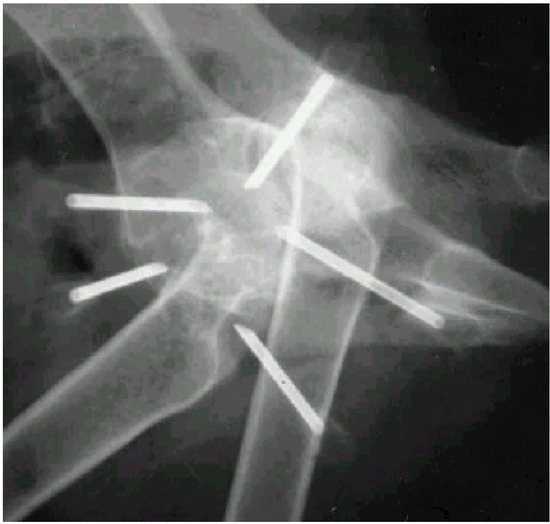

Stainless steel needles (Hypojet® 60 mm × 2.0 mm, 14 G × 2½") (Figure 2) were inserted at an oblique angle at each point and directed towards the joint capsule of the femoral head. The position of the needle tip was adjusted under fluoroscopy (Figure 3). Acupuncture point GB 30 (Point 3) is close to the sciatic nerve. Damage to the nerves was avoided. Any synovial fluid or blood observed from the needle was recorded, and a new needle was reinserted a few mm in another direction. When all the five needles were in place, two gold beads were dropped into each needle through a funnel made from a syringe (Figure 4). A stylet of the same length as the needle was used to push the gold beads just beyond the needle tip and the needle was withdrawn. The skin wounds were covered with liquid plaster (Wound Plast® “Karex”). Both hips were treated in dogs with bilateral HD.

Figure 3. Fluoroscopic evaluation during placement of the needles.

Animals 02 00426 g003

The clinical significance of the ultimate location of the gold beads and points of entry of the needles are not previously discussed in the literature. These questions were not addressed in a systematic way in our study, but they are highly relevant. The choice to use five needles, inserted in three traditional canine acupuncture points and two trigger points, using two gold beads per location [2], were arbitrary decisions. We also decided that the gold beads should be located close to the hip joint capsule, similar to locations described by others [2,3]. The “correct” position of the tip of the needles was facilitated by the use of fluoroscopy (Figure 3). If fluoroscopy is not available, it may be helpful to take radiographs and ensure that the tip of the needle is adjacent to the hip joint capsule before the gold beads are deposited.